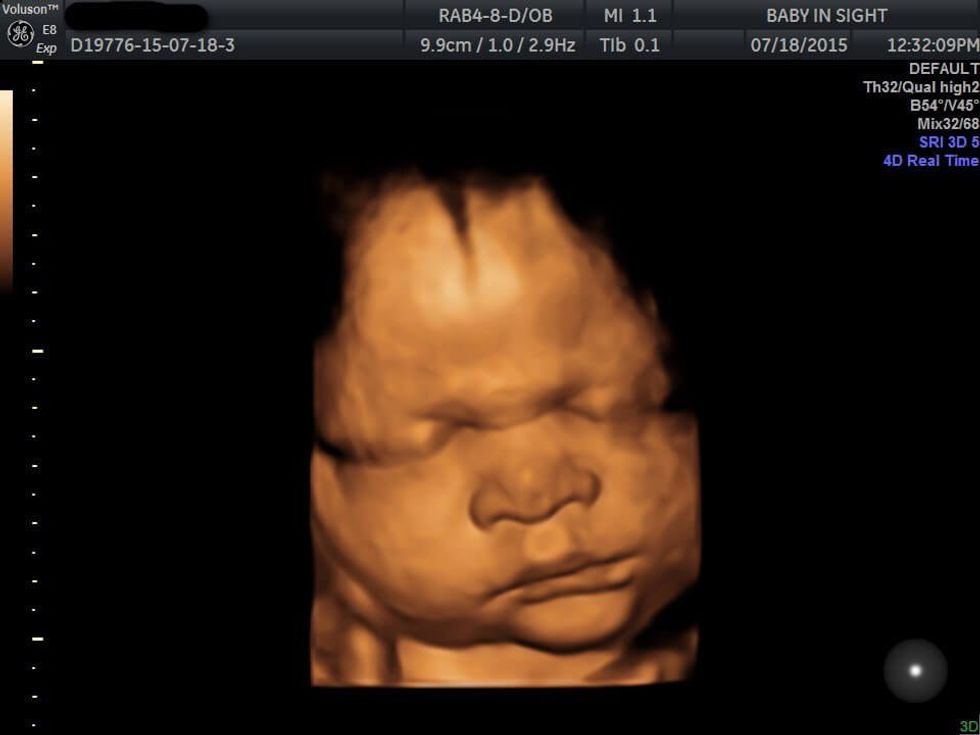

And finally, there is a third trimester abortion. This occurs from 25 weeks – term. At this point in the pregnancy, the baby is almost completely viable and could potentially survive outside of the womb.

On day 1 of the abortion, the abortionist will inject a lethal dose of medicine that is used to treat heart problems into the unborn baby’s head. The baby will feel the needle, because babies can feel pain at this point. The mother will then have to carry her dead child inside of her for a few days while she waits for dilation.

When it’s time for delivery, if she cannot make it to the office, they might advise her to deliver her baby into a toilet or a tub, and the abortionist will come and clean up. If she can make it to the clinic, they will deliver her still-born child.